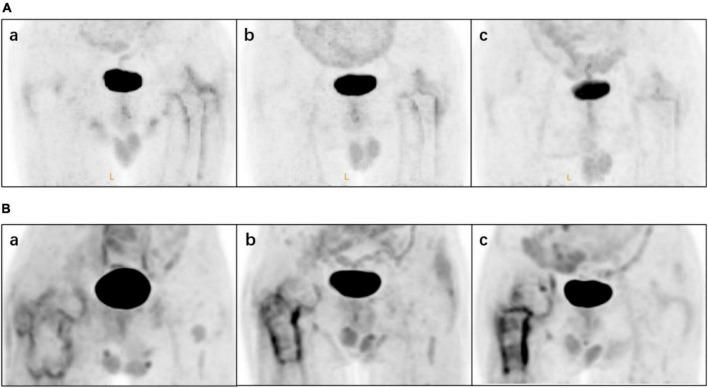

The aim of this study was to retrospectively analyze 18F-fluorodeoxyglucose (F-FDG) positron emission tomography (PET)/ computed tomography (CT) images of non-infected hip arthroplasty patients and summarize findings that may be useful for clinical practice.

F-FDG PET/CT images of non-infected hip arthroplasty patients were collected from September 2009 to August 2021. The region of interest was independently delineated by two physicians and maximum standardized uptake values (SUV) were recorded and compared. Serologic data were also collected and the correlation between SUV and serologic parameters was analyzed, while the images were classified based on the F-FDG uptake pattern in the images using the diagnostic criteria proposed by Reinartz et al. (9). The interval between hip replacement and PET/CT was classified by year and the characteristics of the two groups were compared. The images of patients who underwent PET/CT multiple times were analyzed dynamically.

A total of 121 examinations were included; six patients underwent PET/CT twice and two patients had three scans. There were no significant correlations between SUV and serologic results. The interobserver agreement between the two physicians in the classification according to the criteria of Reinartz et al. (9) was 0.957 ( < 0.005). Although there was non-specific uptake in cases with an arthroplasty-to-PET/CT interval this was non-significant. Additionally, F-FDG showed potential utility for dynamic observation of the condition of the hip.

SUV provided information independent of serologic results, meanwhile F-FDG showed potential applicability to the dynamic monitoring of hip arthroplasty-related diseases. However, the presence of blood vessels and muscles affected image interpretation and the specificity of F-FDG was not optimal. A more specific radionuclide is needed to maximize the benefits of using PET/CT for the assessment of periprosthetic joint infection (PJI).